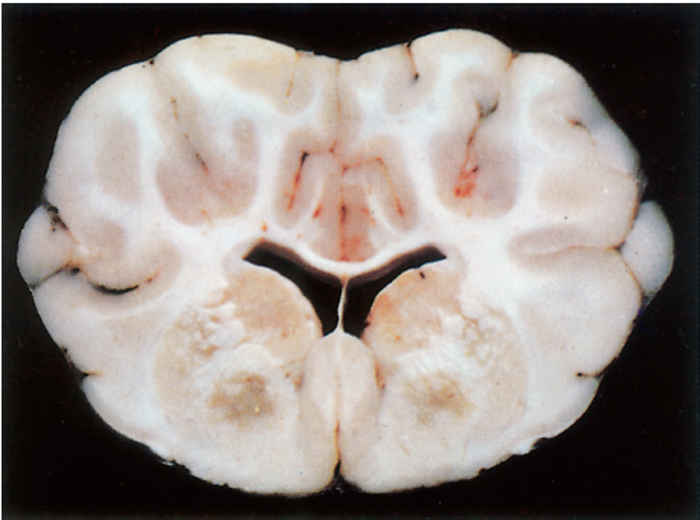

In sheep that have died from FSE, the only lesions consistently present, although they are frequently microscopic, occur in the brain. Those that have suffered from the acute FSE syndrome may also manifest some of the lesions present in pulpy kidney disease. Lesions in the brain are bilaterally symmetrical and two general patterns of distribution are recognized; areas of leukoencephalomalacia may be present in the internal capsule, dorsolateral thalamus, substantia nigra, basal ganglia and cerebellar peduncles,19 the most constant sites being the thalamus and the midbrain areas11 or the white matter of the frontal lobes. Areas of malacia are better seen in formalin-fixed brain tissue.

Three basic histologic lesions occur in the brain of sheep affected by FSE.10 These are widespread perivascular oedema, perivascular haemorrhage and malacia (Figure 180.2). Areas of malacia are always focal and sharply demarcated, and are often accompanied by haemorrhage, but lack an inflammatory reaction.10 Ultrastructurally, there is swelling of astrocytes, the perivascular oedema being caused by their swollen end-feet, and severe damage to vascular endothelium is apparent.11

Additional evidence for the confirmation of the disease may be obtained by histological examination of the brain of sheep. Even though signs of malacia may only be macroscopically present in about 30 per cent of cases, histologically the combined presence of severe oedema, haemorrhages and malacia in the brain stem and midbrain areas is highly suggestive of pulpy kidney disease and is considered by some to be the most reliable way of diagnosing enterotoxaemia in sheep.19 The malacic areas are invariably focal and bilaterally symmetrical.10